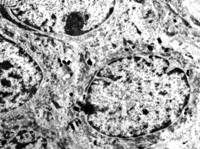

5-2-2 伤后第1天,毛细血管内皮细胞核固缩,管腔内血液凝集和瘀滞 TEM×6000